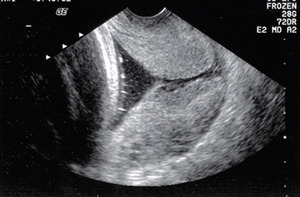

Bardzo istotne jest stosowanie się do standardów badania ultrasonograficznego (rycina).15 Na przykład mocz w pęcherzu matki ma nieprzewidywalny wpływ na ocenę długości szyjki macicy, a technika badania może wpłynąć na jakość otrzymywanych obrazów.16 Z tego względu rekomenduje się szkolenie i certyfikację ultrasonografistów i lekarzy wykonujących pomiary długości szyjki macicy. Szkolenia i certyfikaty oferują online Perinatal Quality Foundation (tj. program Cervical Length Education and Review [CLEAR]) i Fetal Medicine Foundation.15,17